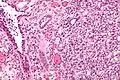

Micrograph of a nephrogenic adenoma. H&E stain.

Nephrogenic adenomas are diagnosed under the microscope by pathologists. Microscopically the tumor shows closely packed small tubular structures in edematous stroma. The tubules show considerable variation in size and shape resembling convoluted tubules of the kidney. The single layer of cells lining the tubules are cuboidal with a scant to moderate amount of cytoplasm. In some areas they may have a hobnail appearance. [2]